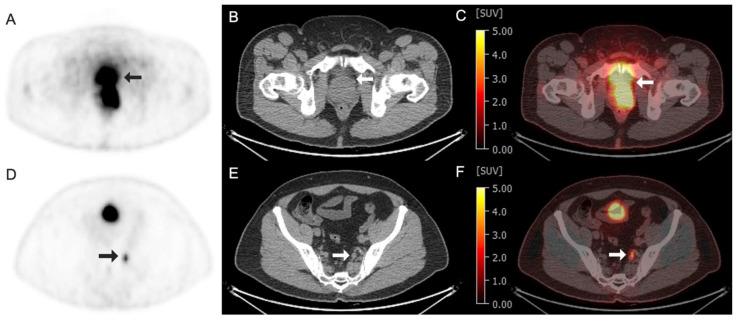

Targeted radioligand therapy (RLT) is an emerging field in anticancer therapeutics with great potential across tumor types and stages of disease. While much progress has focused on agents targeting somatostatin receptors and prostate-specific membrane antigen (PSMA), the same advanced radioconjugation methods and molecular targeting have spurred the development of numerous theranostic combinations for other targets. A number of the most promising agents have progressed to clinical trials and are poised to change the landscape of positron emission tomography (PET) imaging. Here, we present recent data on some of the most important emerging molecular targeted agents with their exemplar clinical images, including agents targeting fibroblast activation protein (FAP), hypoxia markers, gastrin-releasing peptide receptors (GRPrs), and integrins. These radiopharmaceuticals share the promising characteristic of being able to image multiple types of cancer. Early clinical trials have already demonstrated superiority to F-fluorodeoxyglucose (F-FDG) for some, suggesting the potential to supplant this longstanding PET radiotracer. Here, we provide a primer for practicing radiologists, particularly nuclear medicine clinicians, to understand novel PET imaging agents and their clinical applications, as well as the availability of companion targeted radiotherapeutics, the status of their regulatory approval, the potential challenges associated with their use, and the future opportunities and perspectives.

靶向放射性配体疗法(RLT)是抗癌治疗领域中一个新兴的领域,在各种肿瘤类型和疾病阶段都具有巨大潜力。虽然许多进展都集中在靶向生长抑素受体和前列腺特异性膜抗原(PSMA)的药物上,但同样先进的放射性缀合方法和分子靶向技术也推动了针对其他靶点的众多诊疗组合的开发。一些最有前景的药物已进入临床试验阶段,并有望改变正电子发射断层扫描(PET)成像的格局。在此,我们展示了一些最重要的新兴分子靶向药物的最新数据及其典型临床图像,包括靶向成纤维细胞活化蛋白(FAP)、缺氧标志物、胃泌素释放肽受体(GRPr)和整合素的药物。这些放射性药物具有能够对多种类型癌症进行成像的良好特性。早期临床试验已经证明,其中一些药物相对于F-氟脱氧葡萄糖(F-FDG)具有优势,这表明它们有可能取代这种长期使用的PET放射性示踪剂。在此,我们为执业放射科医生,尤其是核医学临床医生提供一份入门指南,以帮助他们了解新型PET成像药物及其临床应用,以及配套靶向放射治疗药物的可用性、监管批准状况、使用相关的潜在挑战以及未来的机遇和前景。